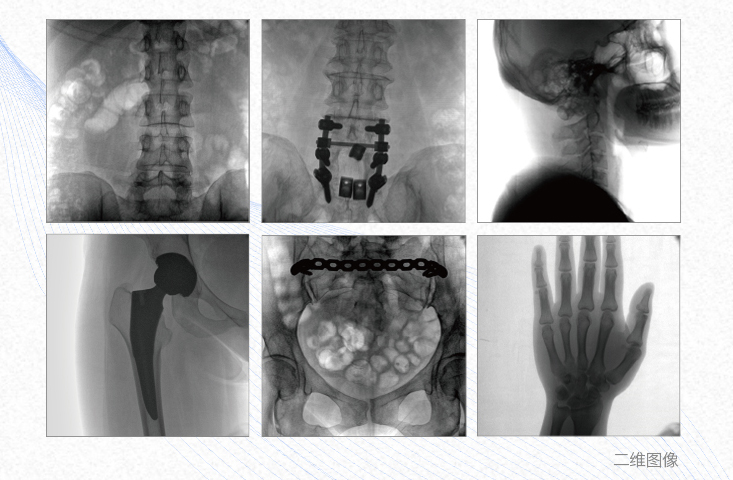

一、平板3DC形臂臨床應(yīng)用廣泛

1、脊柱外科

有效重建復(fù)雜的脊柱三維模型,提供準(zhǔn)確的二維、三維圖像,提高螺釘植入的準(zhǔn)確性,縮短手術(shù)時(shí)間,減少并發(fā)癥的概率,降低輻射的攝入。

2、創(chuàng)傷外科

例如骨盆骨折內(nèi)固定術(shù),可術(shù)中三維重建髖臼關(guān)節(jié)面,準(zhǔn)確定位并植入螺釘,有效縮短螺釘植入的時(shí)間和透視暴露時(shí)間,減少術(shù)中及術(shù)后并發(fā)癥發(fā)生的概率。

3、關(guān)節(jié)外科

主要應(yīng)用于肩關(guān)節(jié)、肘關(guān)節(jié)、髖關(guān)節(jié)、膝關(guān)節(jié)的關(guān)節(jié)置換及解剖復(fù)位的定位。它可以準(zhǔn)確地置入假體,減少輻射時(shí)間,降低輻射劑量。

4、截骨矯形外科

例如治療先天性脊柱側(cè)后凸畸形,可有效引導(dǎo)術(shù)者植入后路螺釘并切除半錐體,達(dá)到滿意的截骨矯正效果。

五、清晰影像助力診斷

*大平板時(shí)代至臻畫質(zhì)    *大功率脈沖射線源    *醫(yī)用彩色診斷監(jiān)視器